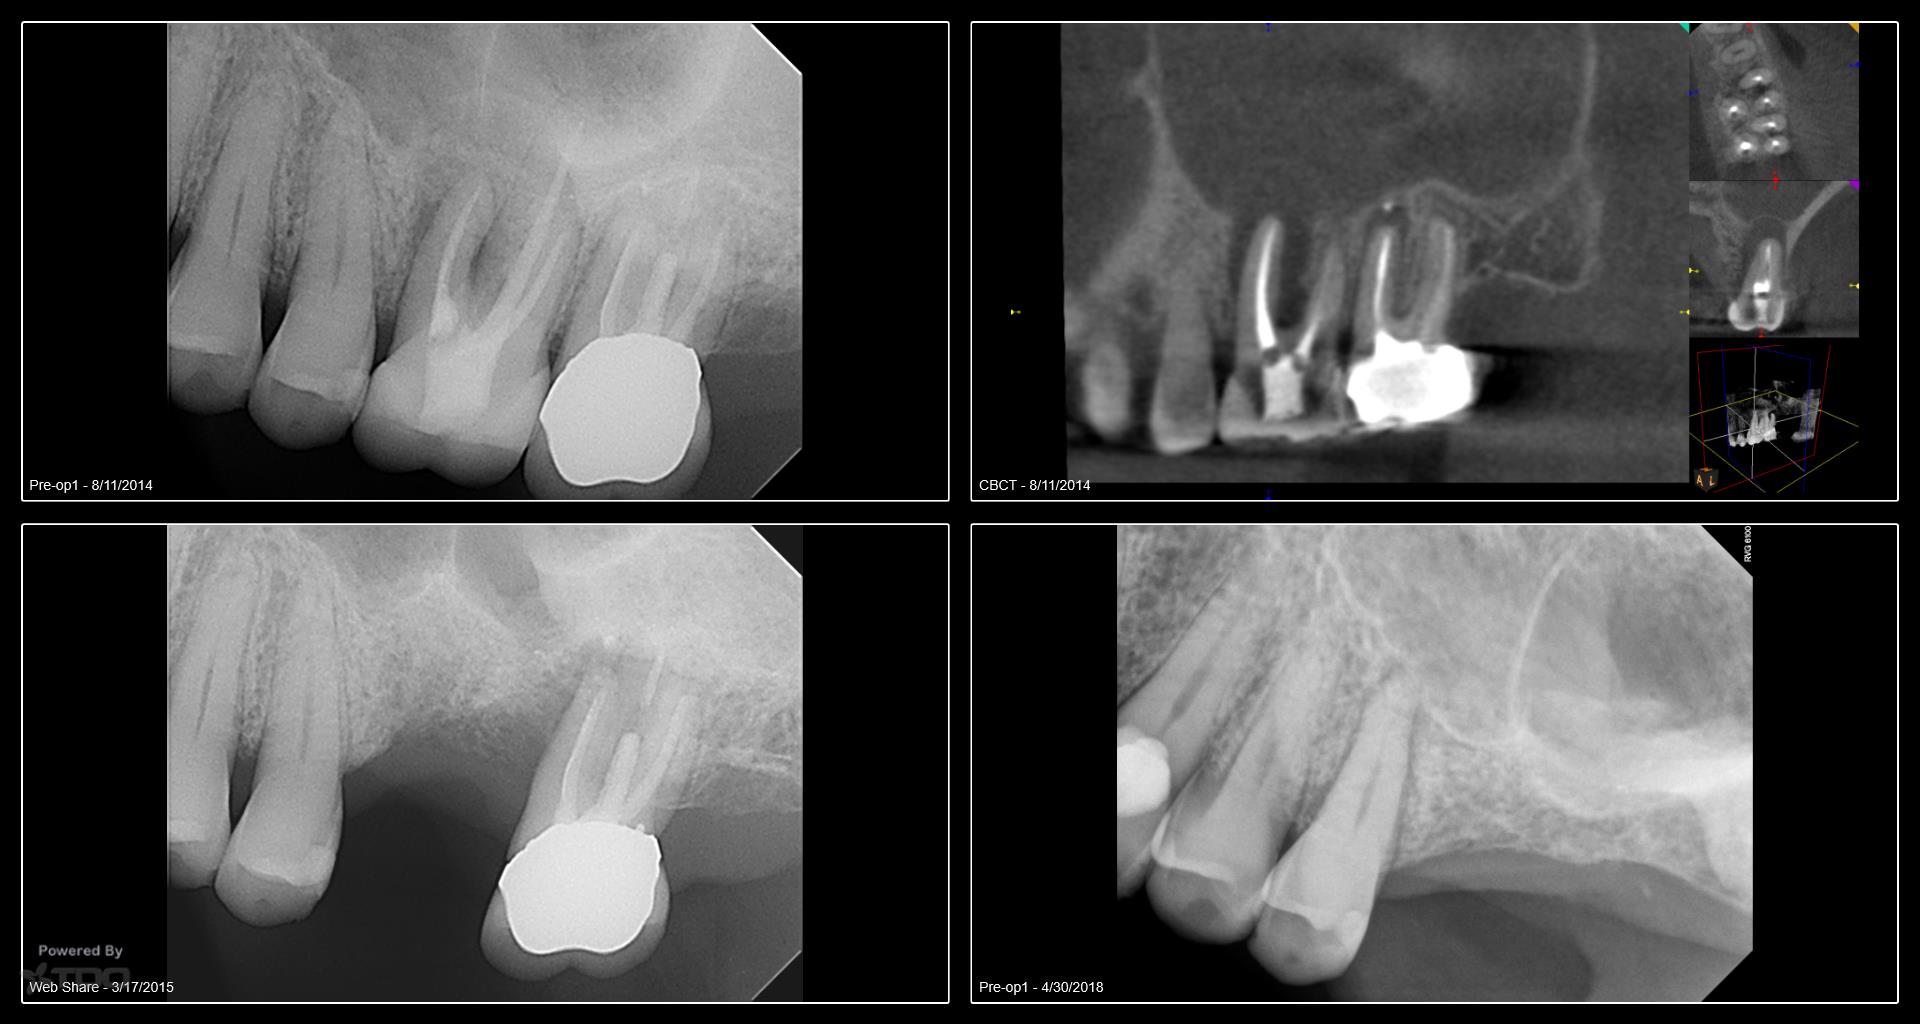

I began seeing this patient in 2014. Tooth #14 was diagnosed with a vertical root fracture at that time and the tooth was removed and the site grafted. He then presented in 2015 with a VRF of #15. It was removed and we discussed an implant in the #14 site. He did not follow up with the implant. He presented earlier this year with a vertical root fracture of #13. The tooth was removed in April and implants were placed today. Internal sinus lifts were performed for both #’s 13 and 14. I will uncover in 4 months. We have also discussed the importance of a night guard. Hopefully he will follow through with the guard. -Charles